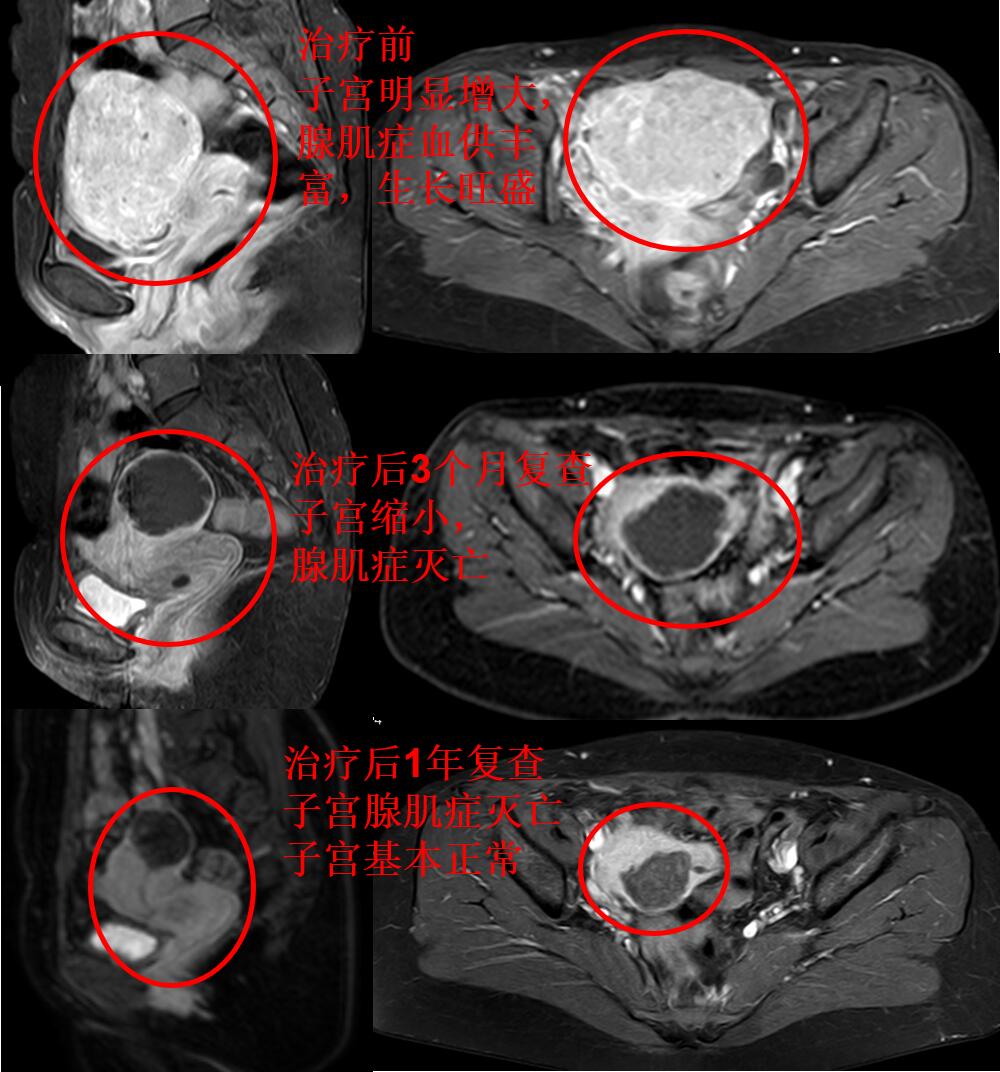

介入微创栓塞治疗后无痛经,3个月复查的磁共振:子宫腺肌症完全灭亡,无血流,子宫缩小,治疗前后对比如下图。

李女士治疗后满1年,痛经没有复发。下图为治疗后1年复查的磁共振图(子宫腺肌症完全灭亡,子宫基本正常(与没有腺肌症的正常妇女的子宫相仿))。